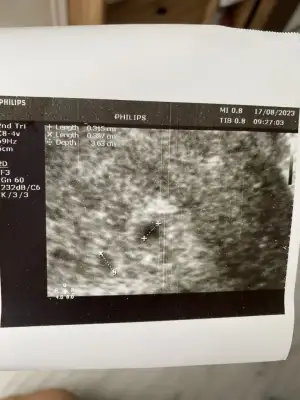

Kızlar günaydın bugün kesemizi gördük çok şükür ☺️ henüz çok küçük karından göremedi vajinal bakalım dedi bir mahsuru yoksa bakalım hocam dedim kesenin yerini görelim iyi olur dedi baktık iki tane kese gördük Allah izin verirse ikizlerimiz geliyor 🤲🏻🥰🧿